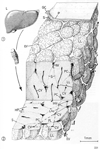

肝臓【かんぞう】 Organ located in the upper right side of the abdomen in the hypochondrium. Its inferior border runs from the upper left to the lower right through the epigastric region. In healthy subjects its border does not reach below the costal margin. It moves with respiration and is thus palpable.(肝臓は身体内の最大の腺であり多様な機能を営むが、それを①胆汁の生産と分泌(腸管内へ)を行う、②炭水化物、脂肪、蛋白の代謝活動、③胃腸管から血液中に進入した最近や異物を細くする、とう3点に要約することができる。(1)位置と形状:肝臓は右上腹部ある巨大な消化腺で、重さは男で1,400g、女で1,200gほどある。色は暗赤褐色で、これは充満する血液によるものである。肝臓の表面が平滑で光沢に富むのは腹膜(の臓側葉)におおわれているからである。肝臓の上面は横隔膜の下面に接して丸く膨らみ、横隔面と呼ばれる。横隔膜上の心臓に対応して、浅い心圧痕をみる。からだの正中にほぼ相当して、横隔面を大きい右半と小さい左半に二分する肝鎌状間膜が走る。これは肝臓の表面を被う腹膜が左右から翻転しながら寄り合い、その間に線維性の結合組織をいれるもので、肝臓を横隔膜から吊り下げる役をしている。このようにして横隔膜と肝臓は平滑な腹膜で自由に滑り動くようになっているが、後部のせまい領域では、両者が線維性結合組織によって密着して活動性に欠ける。肝臓表面のこの領域を無漿膜野(裸の領域Area nuda--腹膜に包まれていない--の意)という。無漿膜野は前方へ細く張り出して肝鎌状間膜につづき、左右へ細く伸びて左三角間膜と右三角間膜になる。左三角間膜の端は、肝臓の左上端を横隔膜につなぐ索をなして線維付属(Appendix fibrosa hepatis)とよばれる。肝臓の上面と下面の境界は前方でうすくするどい縁をなし、下縁(または前縁)とよばれる。上腹部を斜め右下方へ走る一線をなし、触診することができる。これと右肋骨弓の交点に胆嚢の底が腹壁直下に頭を出している。下縁の正中部には肝円索切痕とよぶ切れこみがあって、肝鎌状間膜をはさんでいる。肝臓の下面は上腹部の内臓に面するので、臓側面とよばれる。ここには矢状方向に走る2条のくぼみと、それを横に結ぶくぼみがHの字をなしている。Hの左縦線は前方の半分が肝円索をいえる肝円索裂、後方の半分が静脈管索をいれる静脈管索裂である。Hの右の縦線には前方に、胆嚢の上面をおさめる胆嚢窩があり、後方に大静脈をおさめる大静脈溝がある。H字の横線に当たる溝は肝門で、門脈、固有肝動脈、肝管のほか多数のリンパ管と若干の神経が通っている。肝鎌状間膜、肝円索裂、静脈管索裂によって、肝臓は大きい右葉と小さい左葉に分けられる。肝臓の臓側面では、右葉(広義)が胆嚢窩、大静脈溝、肝門によって狭義の右葉、中央前方の方形葉、中央後方の尾状葉に分けられる。尾状葉は全科法へ乳頭突起を出し、前右方へ、肝門の後縁に沿って尾状突起を出す。乳頭突起に対峙して左葉から小綱隆起が張り出し、両者の間に小綱をはさむ。(2)肝臓の構築:肝臓の表面は大部分腹膜をかぶり、その下に線維性の結合組織がある。この結合組織は大血管とともに肝臓内に侵入し、血管周囲線維鞘をつくる。ギリソン鞘(Glisson's sheath)ともよばれる。肝臓の実質は径1mm前後の短六(ないし五)角柱の肝小葉を構造単位として成り立っているが、肝門からはいる肝固有動脈と門脈の枝はグリソン鞘を伴って、この肝小葉の稜線(三つの肝小葉の合するところ)に沿って走るこの動静脈を小葉間動・静脈とよぶ。肝小葉の角柱の中心を貫いて中心静脈という太い毛細血管が走り、その周囲に肝細胞の板が放射状に配列する。肝細胞板(hepatic cell plates)は分岐し、吻合し、あなをもち、すきまに洞様毛細血管(sinusoidal capillaries)をいれている。小葉間動静脈の枝は小葉の洞様毛細血管に注ぎ、中心静脈から、小葉下静脈(Vena sublobularis)とよばれる小静脈を経て下大静脈へと流れていく。肝細胞板の中に、肝細胞のあいだを縫って走る細管系が毛細胆管(bile capillary)であって、肝細胞の産生する胆汁を運ぶものである。毛細胆管は肝小葉のへりで小葉間胆管とよばれる小導管に注ぎ、グリソン鞘の中を合流しつつ肝門へ向かう。(3)肝臓と血管:肝臓は門脈の番人というべき器官である。すなわち消化管から送られてくる血液中に余分の糖分があればグリコゲンとして貯え、有害物質があれば分解、解毒する。脾臓から送られる破壊血液のヘモグロビンをビリルビンに変えて胆汁中に排泄する。門間区によって運ばれてくる膵臓のホルモンは、肝細胞でのグリコゲンの産生とブドウ糖への分解を調節する。しかし、門脈血は酸素に乏しい静脈血であるから、肝臓は動脈血を固有動脈にあおがねばならない。胎生期においては、臍から前腹壁を上行して肝臓の下面に達する臍静脈(Vena umbilicalis)が、肝門で門脈と合して、そのまま肝臓の下面を後方へ走り、下大静脈に注ぐ。細静脈と下大静脈のこの短絡路を静脈管またはアランチウス(Arantius)の管と称する。生後、胎生期の循環路は閉鎖し、結合組織索として残る。臍静脈の遺残が肝円索、静脈管の遺残が静脈管索である。 (解剖学事典 朝倉書店より引用) 肝臓の生理 肝臓は重要な機能を営む器官であり、肝臓を楔状すると12時間前後で低血糖で死亡するといわれている(動物実験では70%の肝切除でも数週で機能が正常になるといわれている)。)

12-1.前腸

12-4.後腸